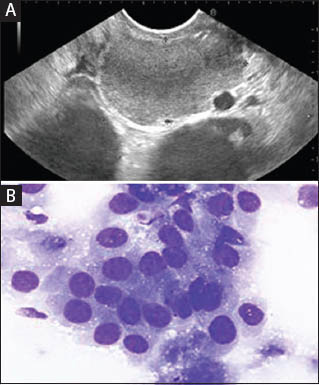

This article reports the findings of a pleural fluid with features characteristic of malignant mesothelioma. In this patient, cirrhosis was initially considered but ct evidence suggested malignancy‐related peritoneal. Pleural effusions, for instance, may occur in malignant pleural mesothelioma patients, where fluid builds up in the lungs. In patients with a malignant mesothelioma (mm), pleural effusions are common and often recurrent, providing an opportunity in some cases for early diagnosis, 1 particularly because sampling the fluid is minimally invasive and serial collections are easily performed. Most patients have an effusion at the time of presentation.

The diagnosis of malignant mesothelioma by cytology has been accepted in the last decade and guidelines for the diagnosis were previously published. In an effort to estimate the practice at other institutions, a survey was disseminated regarding cytologic diagnosis of mm. To provide practical guidelines for the cytopathologic diagnosis of malignant mesothelioma (mm). Survival with the epithelioid subtype of malignant mesothelioma (mm) is longer than the biphasic or sarcomatoid subtypes. malignant mesothelioma malignant mesothelioma seek now. The designations of 'malignant mesothelioma, cannot exclude mmis' Sporadic bap1 mutations are common and are associated with improved survival. The objective of this study was to define the role of cytologic examination of pleural fluid in facilitating early diagnosis. Rakha ea, patil s, abdulla k, et al. In this patient, cirrhosis was initially considered but ct evidence suggested malignancy‐related peritoneal. Even though the diagnosis of malignant mesothelial proliferations can be established in fluid specimens, the diagnosis of mesothelioma in situ cannot be made in cytology specimens, and the tissue. Conversely, elevated levels of hyaluronic acid (ha) in effusions are. Hjerpe, a, ascoli, v, bedrossian, cw, boon, me, creaney, j, davidson, b, et al.

It is at gift possibly to incorporate some errors and is provided for fashionable. Germline bap1 mutation has been associated with early onset and less aggressive disease compared with sporadic mm. The cytology of malignant mesothelioma. A conclusive diagnosis of malignant mesothelioma (mm) can be based on effusion cytology using the guidelines for the cytopathologic diagnosis of epithelioid and mixed‐type mm. The cytologic criteria for the diagnosis of mm in an effusion specimen are well established.

Rakha ea, patil s, abdulla k, et al. cytology of atypical mesothelial cells: To conduct cytology research, doctors will first take a fluid biopsy. Correlation between pleural fluid cytology and magnitude of pleural invasion in patients with malignant pleural mesothelioma amr m. Cell groups with scalloped borders.

This list affords a subset of the read code device primarily based on public domain information. Complementary statement from the international mesothelioma interest group, also endorsed by the international academy of cytology and the papanicolaou society of. Read "changing clinical course of patients with malignant mesothelioma: The designations of 'malignant mesothelioma, cannot exclude mmis' 5byte read codes, version three.1. malignant pleural mesothelioma (mpm) is a highly aggressive malignant tumor that arises from mesothelial cells of pleural cavity. Bap1 is a tumour suppressor gene commonly mutated in mm. Mesothelial cells in large groups. The diagnosis of malignant mesothelioma in effusion cytology: The pathology of malignant mesothelioma, focusing on the most common form, diffuse pleural malignant mesothelioma, will be reviewed here. The cells had large, round, centrally located nuclei with vesicular. malignant mesothelioma arises most commonly in the pleura and rarely in the peritoneum. The diagnosis of malignant mesothelioma by cytology has been accepted in the last decade and guidelines for the diagnosis were previously published.